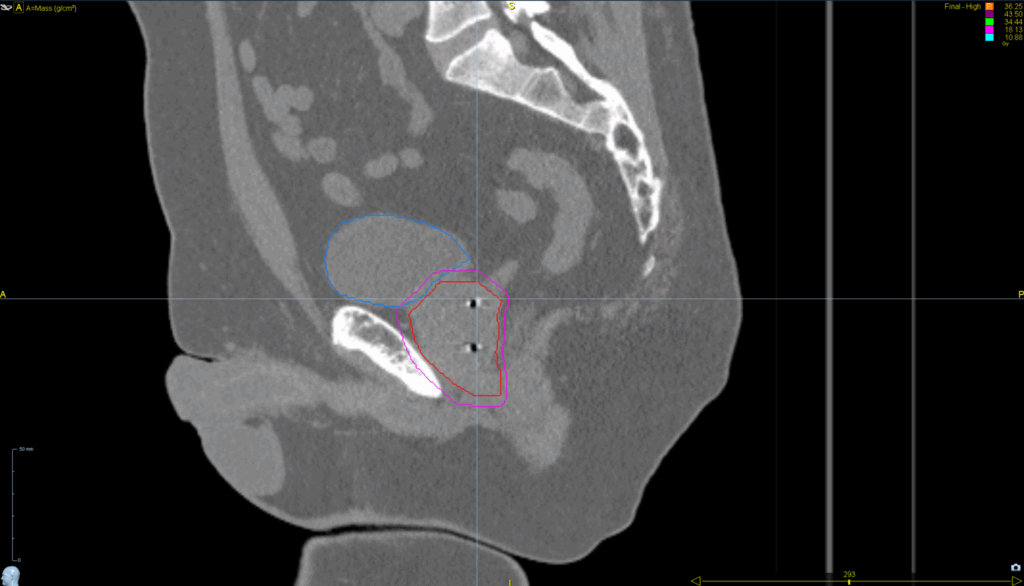

Planning CT Images